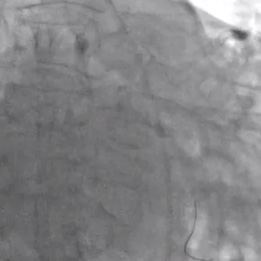

• La cuerda guía original se cambió utilizando un balón OTW por una cuerda guía RotaWire ™

• Se avanzó una oliva de 1,5 mm y se realizó una aterectomía rotacional.

• Posteriormente se hizo aterectomía con una oliva de 2,0 mm.

• Se evaluó la lesión y se predilató a presión alta con un balón NC Quantum Apex de 3,25 x 15 mm.

• Se colocó un stent liberador de fármaco (DES) de 3,5 x 16 mm con excelente expansión mediante fluoroscopía.